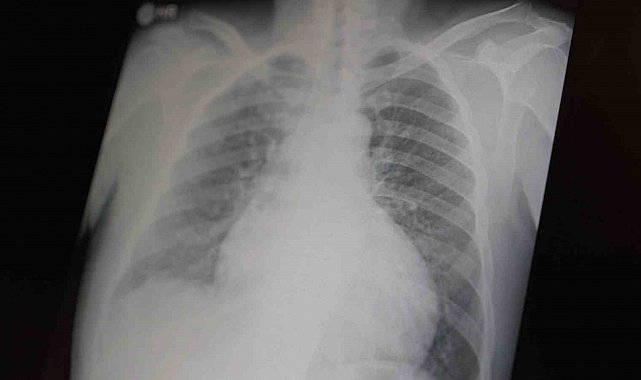

Prof. Dr. Şevket Özkaya, çocukları ve gençleri etkileyen bağımlılıklar hakkında açıklamalarda bulundu. Metamfetaminin sentetik bir uyuşturucu olduğunu ve kullanımının ölümcül sonuçlar doğurduğunu ifade eden Özkaya, "Tüm dünyada çocukları ve gençleri etkileyen iki önemli bağımlılıktan bahsetmek istiyorum. Bunlar metamfetamin ve kokain bağımlılığıdır. Metamfetamin en ölümcül, en çok bağımlılık yapan, okul çağında en kolay ulaşılabilen bir sentetik uyuşturucudur. Kullanıma bağlı ciddi akciğer ve karaciğer sorunları ortaya çıkıyor. Çok küçük dozlarda bile anında bağımlılık yapabiliyor ve tedaviyle bırakılması çok zor bir bağımlılıktır" dedi.

Açıklamalarında, her iki uyuşturucunun beyin hasarı oluşturduğunu ve nöro sinir hücrelerini harap ederek solunum ve kalbin durmasına sebep olduğunu vurgulayan Özkaya, "Metamfetamin tüm dünyada bir sorun olmanın ötesinde, ülkemizde de gençlerimizi etkileyen toplumsal bir sorun olarak görülmelidir" ifadelerini kullandı.